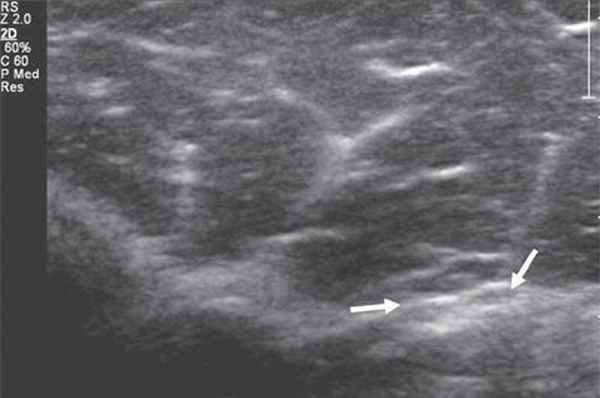

Рис. 1. Поперечная сонограмма лучевого нерва (короткие стрелки) на уровне спирального канала плечевой кости (длинные стрелки - контур плечевой кости).

Именно со спирального канала целесообразнее всего начинать процесс сканирования лучевого нерва. Как правило, для этого используются датчики с частотой 9-17 МГц, и исследование проводится преимущественно в поперечной проекции. Далее, тотчас кпереди от латерального надмыщелка плеча, n. radialis делится на чувствительную (или поверхностную) и двигательную (глубокую) ветви и задний межкостный нерв (рис. 2).